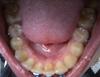

Правда,сейчас на ВЧ начал образовываться промежуток между единичками (на фото заметно уже). Я вообще никогда не думала, что у меня когда-нибудь будет щель между передними зубами, но это процесс лечения. У меня просто Вч не симметрична,поэтому сейчас основной упор на выравнивание центра

. Приходиться мириться с этим переходным положением зубов... ![]()

Еще на приеме я пожаловалась ортше,что на нч "забор" никак не может выровняться. Пожаловалась! ортша сказала,что всё выровняется и поставила железную лигатуру на "упрямый " зуб, не желающий уступить место соседу. В этот же день , часа через 3-4 , смотрю в зеркало и не верю: все стали ровно в ряд!

Хоть эти 4 передних зуба на нч ещё не ровно стоят, но по крайней мере забора явного нет. УРА!

Вообщем выкладываю фото ,судите сами....